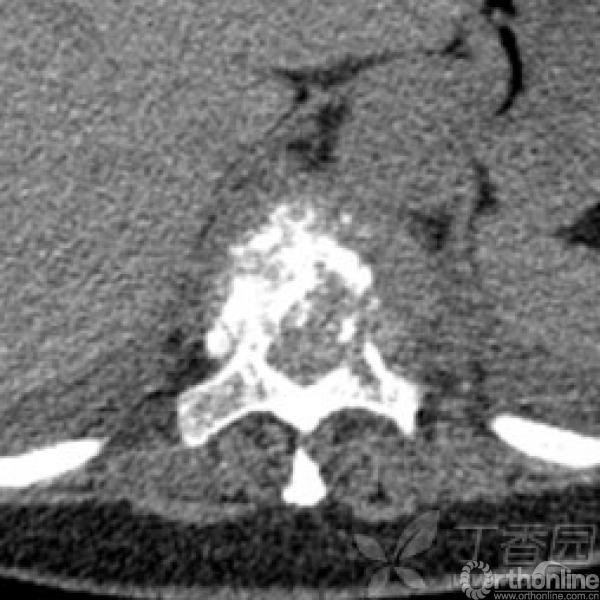

胸椎多椎体病变,如果诊断和治疗?